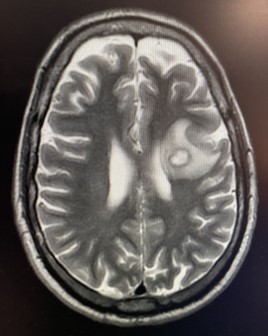

You are practicing telemedicine and are asked to make a diagnosis in a 53-year-old

man who presents with a chief complaint of "difficulty speaking" of several weeks

duration. His past medical history is positive for hypertension, a "resolved" squamous

cell carcinoma of his left nasal vestibule, and for a nodular thyroid. CT and MRI

scans of his brain are showed below.

DIAGNOSIS: glioblastoma with expressive (Broca's) aphasia.

The classic MRI finding in patients with glioblastoma is an irregularly shaped rim-enhanced

or ring-enhanced lesion with a central dark area of necrosis.

The coronal T2W MRI shows an irregular ring-enhanced lesion with a small area of central necrosis - all characteristic of a glioblastoma. The white area around the tumor is due to edema. Note the tumor is compressing the lateral venricle. One can see the tumor involves Broca's area, accounting for the patient's expressive aphasia.